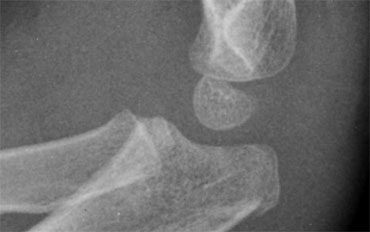

Fragmented appearance of the Trochlea in 2 different children. Fragmented appearance of the Trochlea in 2 different children.

The Trochlea has two or more ossification centres which can give the trochlea a fragmented appearance.

Trochlea ossification-fragments simulate loose bodies in the joint Trochlea ossification-fragments simulate loose bodies in the joint

On a lateral view the trochlea ossifications may project into the joint.

They should not be mistaken for loose intra-articular bodies (arrow).